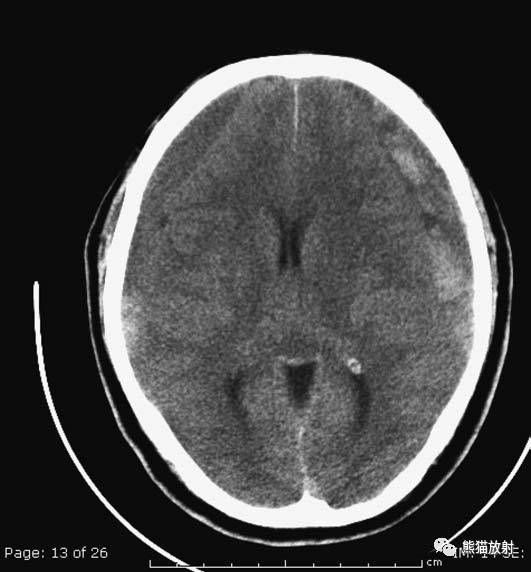

双侧等密度硬膜下血肿